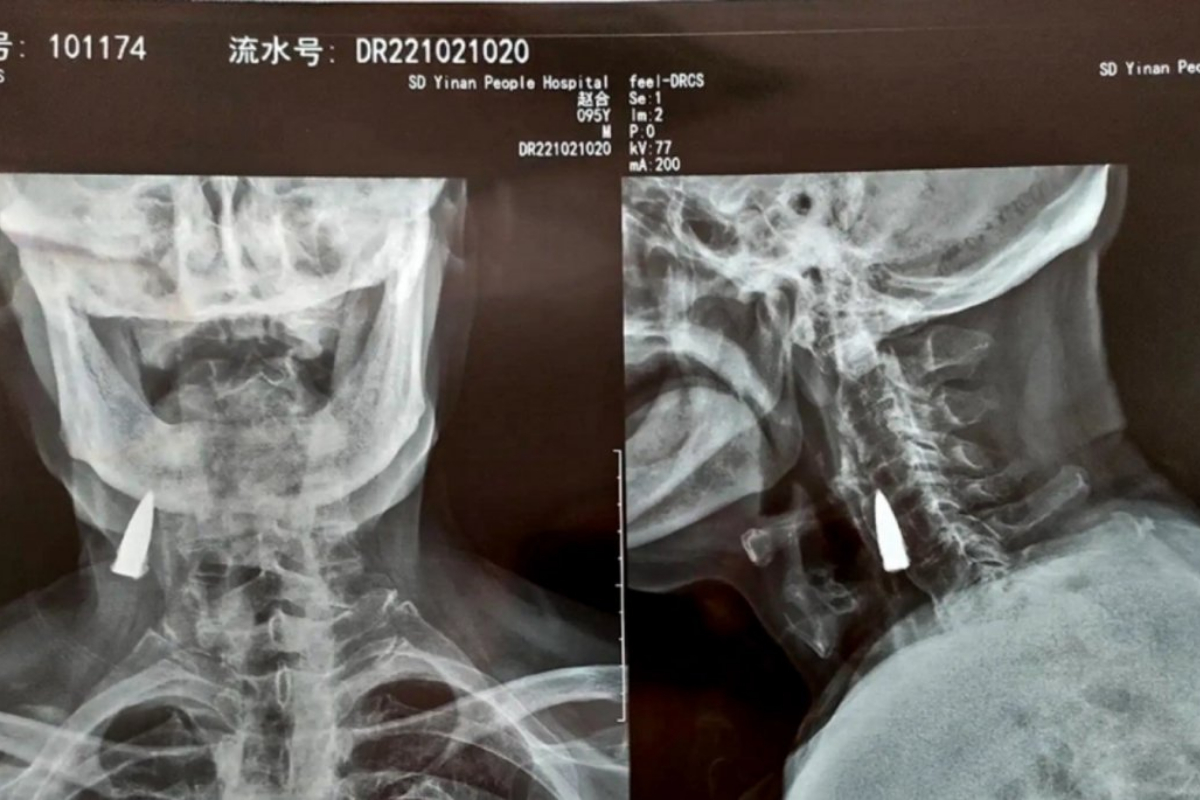

X-ray Reveals WWII Vet’s Bullet Stuck in Neck for 8 Decades

A World War II veteran was surprised to learn that a bullet from the conflict remained lodged in his neck nearly 8 decades later. According to the media sources, the combat veteran identified as Zhao He is a Chinese citizen. During the devastating World War II, the 95-year-old got a bullet stuck in his body. However, the mayhem and commotion at the moment were so intense that he didn’t even notice its presence till the conflict was ended. It wasn’t until recently that medical personnel at a hospital in Shandong, China, discovered the bullet during an X-ray of Zhao He’s neck.

“He was injured while carrying a wounded comrade across a river during one of the battles. There is shrapnel in other parts of his body as well,” he stated. Doctors call it a wonder that the trapped bullet hasn’t caused any problems for the old despite being in his body for nearly 77 years. The medical team has chosen not to remove the bullet from his body because it has not yet caused any harm. Furthermore, given the elderly’s age, the procedure would entail dangerous surgery. “I’ve been healthy all these years so there is no reason to change things now,” the combat veteran agreed with the medical specialists.”